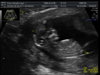

Czarownica no ba przeciez wiadomo ze pesteczka to O.N.A. Gratki gratki gratki widzę ze życzenia Wam sie spełniają!!!!! Chyba kazdej co chciała to ma.

Gratulacje! Jakie super foty!

Gratuluję, super! Ale Ci zazdroszczę tej dziewczynki.

Ja też strasznie bym już chciała wiedzieć! A jeszcze muszę czekać 2 tygodnie do wizyty...Czarownica gratuluję!!! Śliczna [emoji7][emoji7]